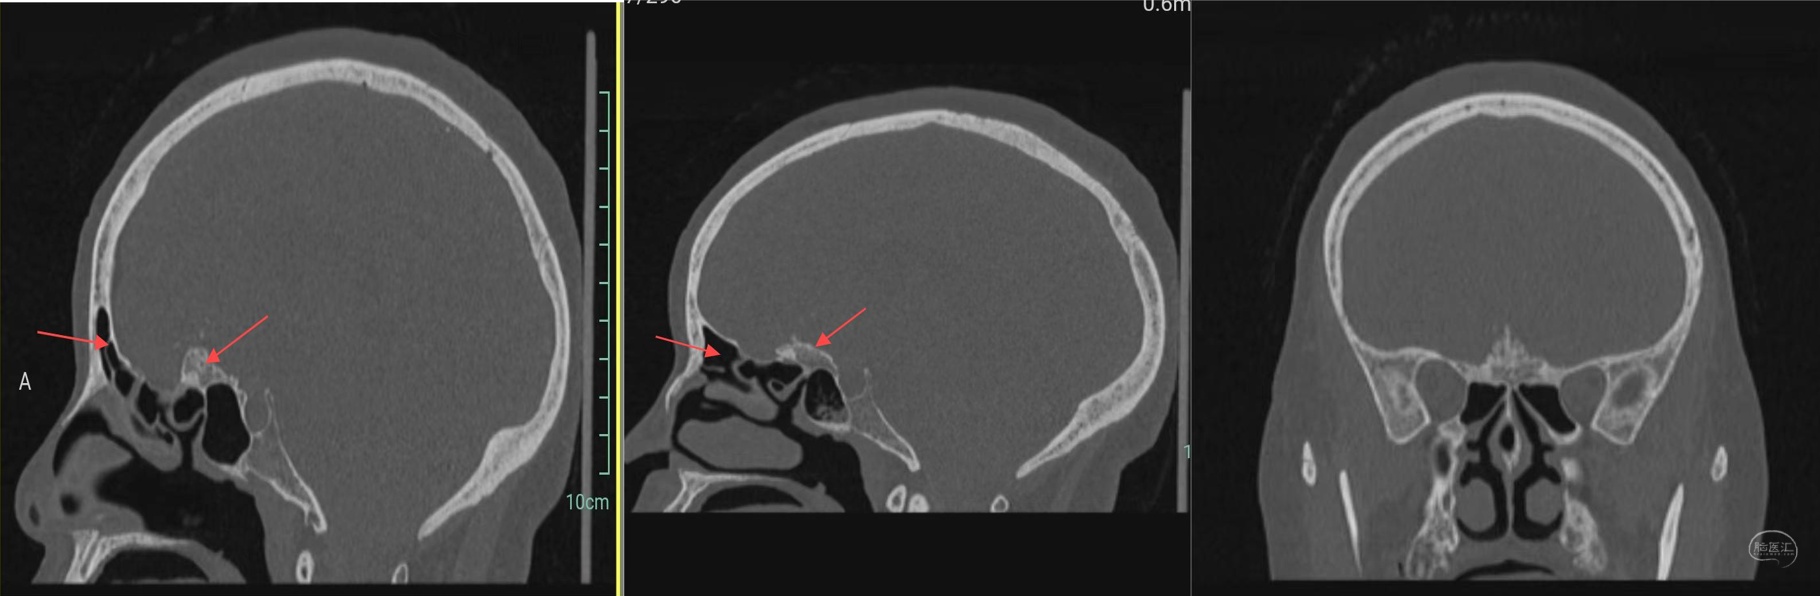

颅脑CT:前颅底占位性病变,颅底骨质增生,瘤内钙化,周围脑组织水肿。

颅骨冠矢状位重建示前颅底骨质明显增生,额窦发达。